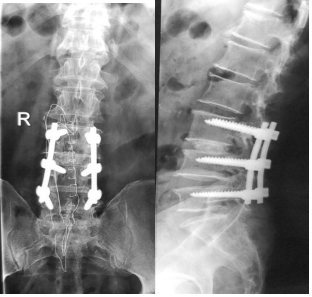

3.腰椎椎管狹窄行腰椎椎間盤切除椎間植骨融合內(nèi)固定術(shù)后